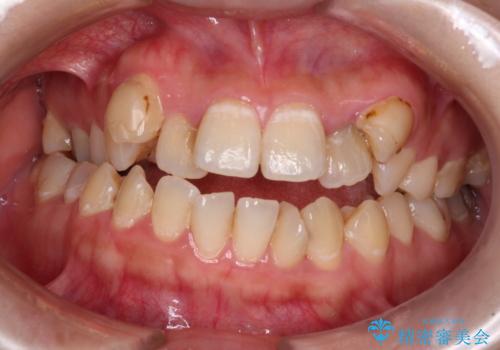

- デコボコと飛び出した前歯を治したいとのことで来院された患者様です。

ゴムかけを活用して上顎歯列全体を後方移動し、IPR(歯と歯の間を削る)によってデコボコが解消するように設計し、インビザラインにより治療を行うこととしました。

後方移動に際し、上下顎の親知らずは4本とも抜歯することとしました。